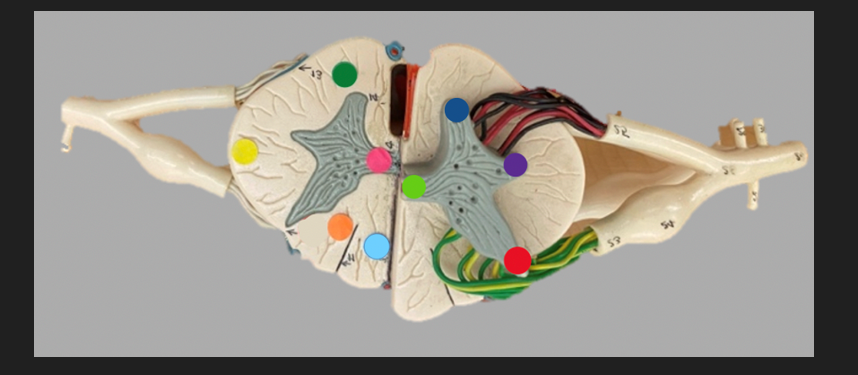

green dot

spinal nerve

orange dot

ventral root

pink dot

dorsal root

blue dot

dorsal root ganglion

red dot

dorsal ramus

yellow dot

ventral ramus

purple dot

anterior median fissure

red dot

posterior (dorsal) horn

purple dot

lateral horn

dark blue dot

anterior (ventral) horn

orange dot

dorsal column

yellow dot

lateral column

dark green

anterior column

line green and pink doit

gray commissure

light blue dot

posterior median sulcus